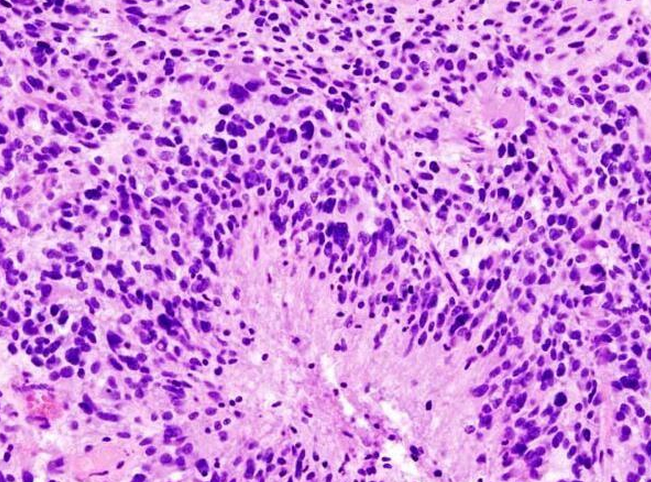

近日,来自美国西北大学的研究人员通过研究利用球形核酸开发出了首个能够用于人类机体全身性治疗的药物,目前这种球形核酸药物已经获得FDA批准,并且作为一种试验性新药正在处于多形性胶质母细胞瘤的早期临床试验中。

这种新药能够跨越血脑屏障直接进入动物模型大脑的肿瘤患处,在肿瘤位点该药物能够关闭关键的促癌基因的表达,目前正在进行的0期临床试验就在调查该药物是否能够直接到达人类机体的肿瘤位点。治疗胶质母细胞瘤的药物代表了一类革命性的新型药物,研究者表示,这种新型的球形核酸平台还能够用于对其它神经变性疾病进行研究,比如阿尔兹海默病和帕金森疾病,其能够通过类似的作用机制来关闭诱发多种神经变性疾病的基因的表达。

通常研究人员利用化疗、放疗和外科手术的方法来治疗胶质母细胞瘤患者,但针对该疾病目前并没有有效的治愈手段,在美国每年大约30000名个体会被诊断为恶性脑癌,而且患者的预期寿命仅为14-16个月。研究者Priya Kumthekar教授说道,我们迫切需要一种能够治疗这种恶性疾病的有效疗法,这项研究中,我们招募了肿瘤复发的患者以及肿瘤移除的候选者进行研究,在患者进行外科手术之前首先通过静脉注射这种新型药物,当肿瘤被移除后,我们将会对肿瘤的药物成分进行研究确定这种新型药物是否能够有效跨越患者的血脑屏障对肿瘤实施精准打击。

2013年,研究者Stegh和Mirkin就通过联合研究在Science Translational Medicine杂志上发表了他们的研究成果,他们首次描述了利用静脉注射运输药物可以关闭胶质母细胞瘤中关键的促癌基因,同时还能够降低肿瘤的进展,明显增加患病小鼠的生存率。在患胶质母细胞瘤的小鼠机体中,大约1%的注射剂量药物就能够有效在颅内大脑肿瘤组织中积累,更有意思的是,这种新型的球形核酸还能够选择性在肿瘤位点进行积累,这很有可能是由于肿瘤能够产生渗漏的血管,使纳米颗粒具有能够仅在肿瘤组织中积累的能力。

相比对照组小鼠而言,接受新型疗法治疗的动物模型的生存率能够增加大约20%,而且肿瘤尺寸也会明显下降3-4倍。研究者Mirkin在1996年首次通过研究开发出了这种纳米平台,同时研究者们也首次意识到将这种纳米结构注射到动物模型体内能够帮助寻找大脑中的肿瘤靶点,并且将有效的药物运输到肿瘤位点实施精准打击。未来研究者们还将通过更为深入的联合研究来检测这种新型的球形核酸药物在治疗多种脑瘤中的作用效力